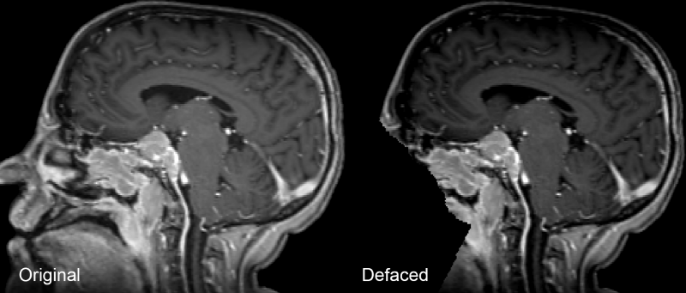

All radiotherapy planning images underwent pre-processing. This included conversion from DICOM and DICOM-RT to Neuroimaging Informatics Technology Initiative (NIfTI) image file format using dcmrtstruct2nii followed by automated defacing using the Analysis of Functional Neuroimages toolbox (AFNI) as seen in Figure 6 (Cox, 1996; Cox and Hyde, 1997; Phil et al., 2023).

This decision was made due to the superior performance of increased inclusion of meningioma tumors within the respective pre-processed brain MRI using the AFNI defacing method compared to other defacing algorithms (Cox, 1996; Cox and Hyde, 1997; Theyers et al., 2021).

Refer to caption

Figure 6: Example of a brain MRI before and after automated defacing.